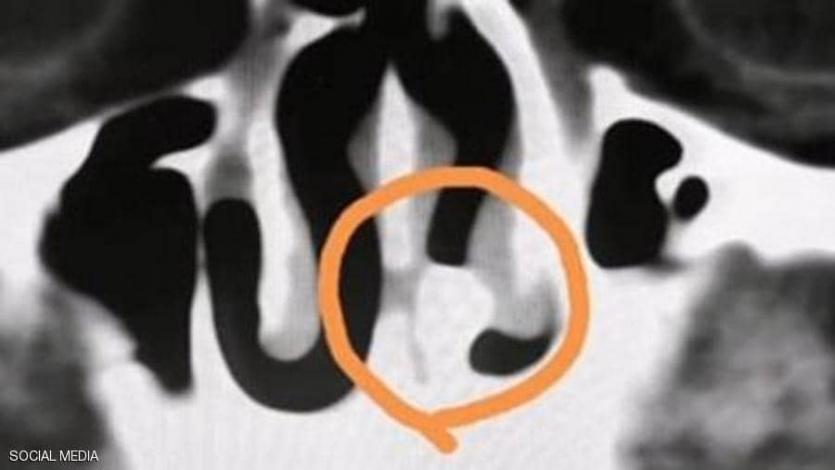

وأثناء الفحص بالأشعة السينية، لاحظ الأطباء وجود جسم ذو كثافة عالية في الجزء الخلفي من تجويف الأنف.

وقال أحد الأطباء: "لقد بدا الأمر وكأنه سن".